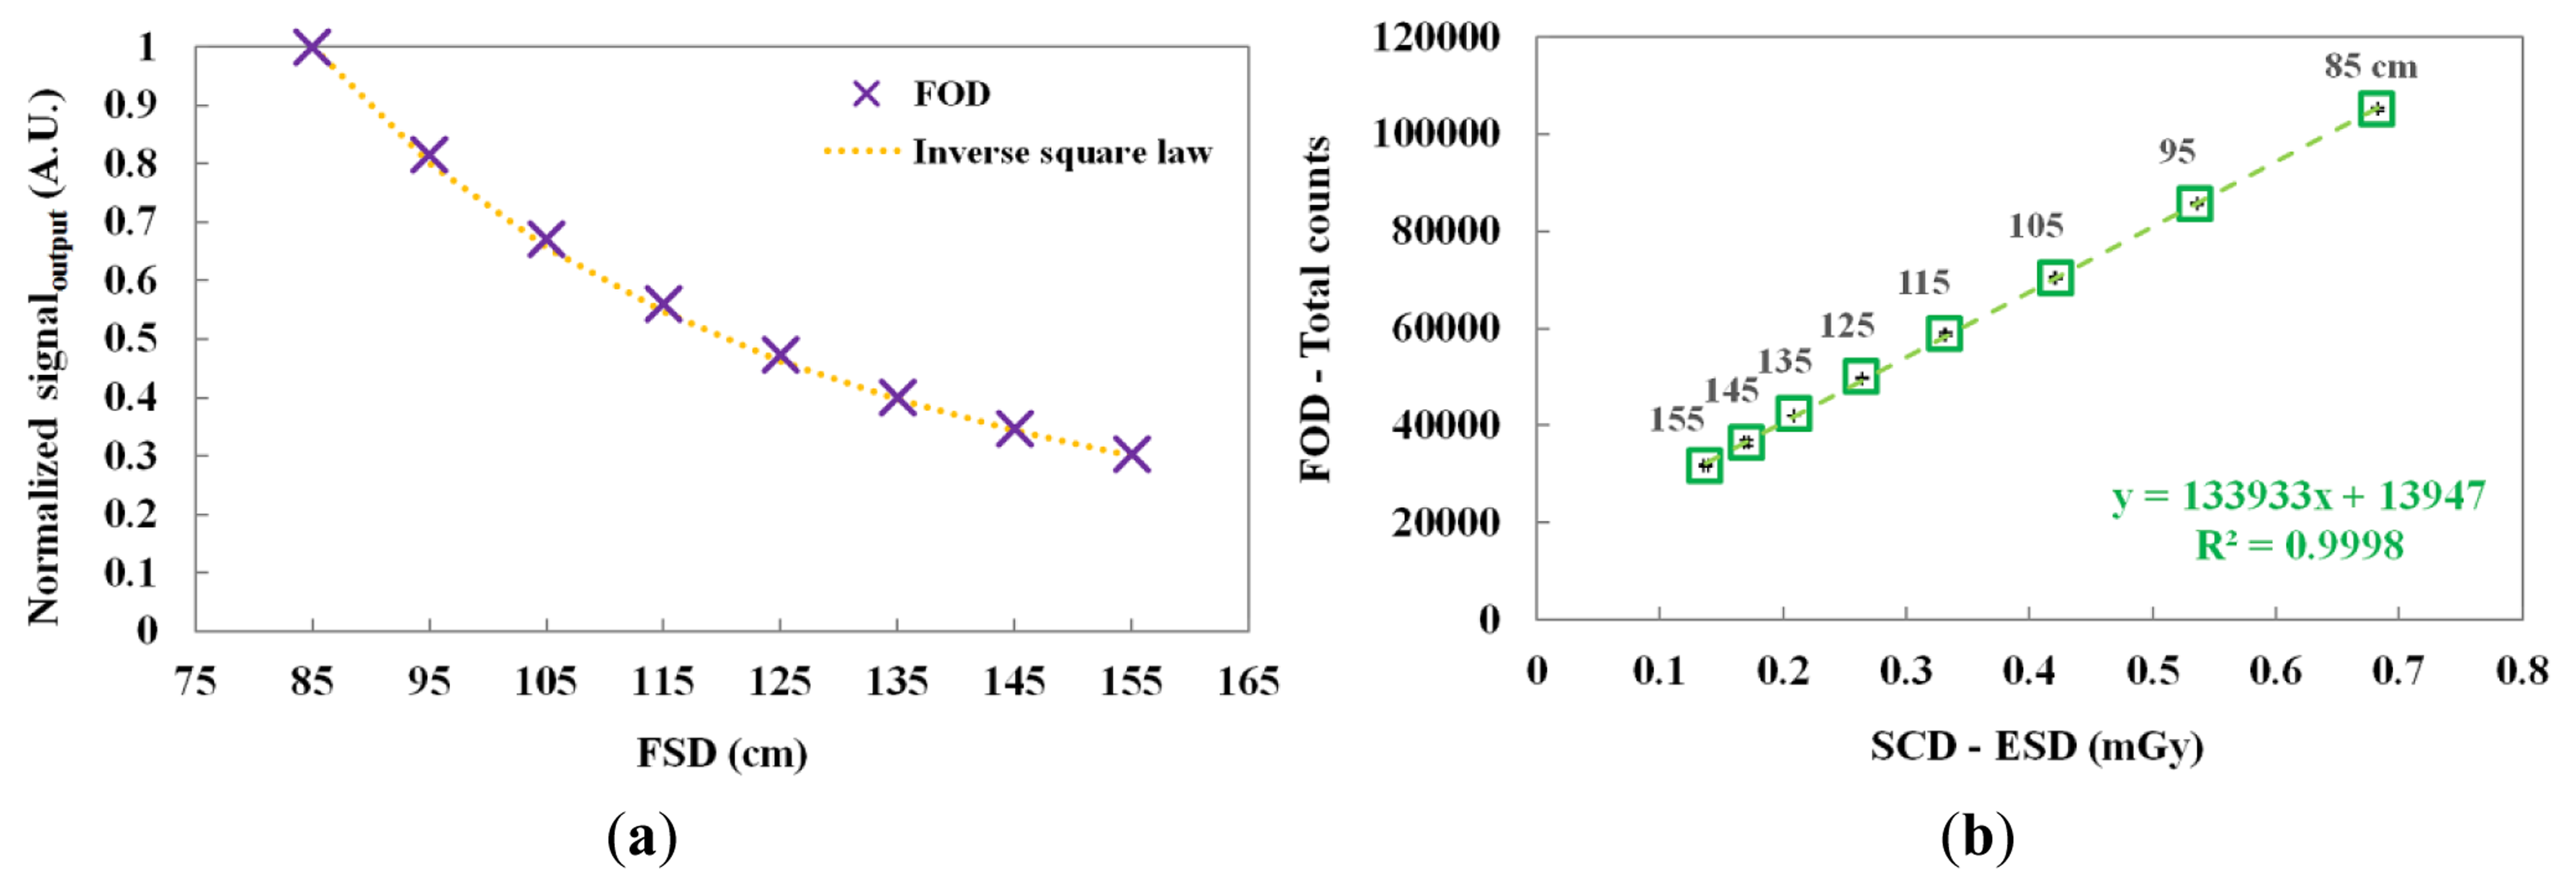

The scintillating light and the ESD were measured by increasing the FSD from 85 to 155 cm. Figure 8a,b shows the normalized output signals of the FOD at each FSD and the relationship between the total counts of the FOD and the ESDs of the SCD according to the FSD, respectively. As the FSD increased, the total counts of the FOD and the ESDs of the SCD decreased. In addition, the normalized output signal of the FOD and the theoretical value of the inverse square law were very similar over the distance between the focus of the X-ray tube and the sensing probe placed on top of the thorax phantom.